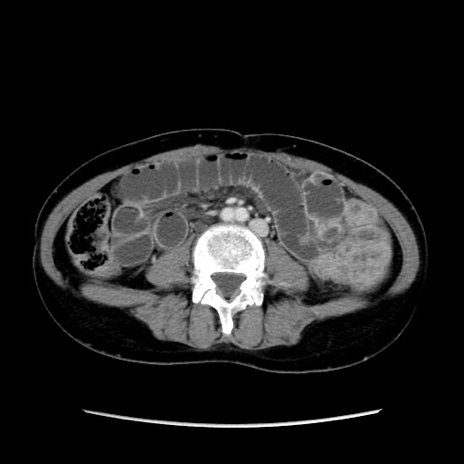

矢状断像

【症例】40歳代 女性

【主訴】上腹部痛、嘔気・嘔吐

【現病歴】約9時間前頃から急に上腹部痛、嘔気、嘔吐が出現。改善しないため救急要請。

【既往歴】子宮頚癌(広汎子宮全摘術、放射線療法)、腸閉塞

【身体所見】腹部:平坦、軟、腸雑音亢進、上腹部を中心に腹部全体に圧痛あり。

【データ】WBC 8400、CRP 0.03